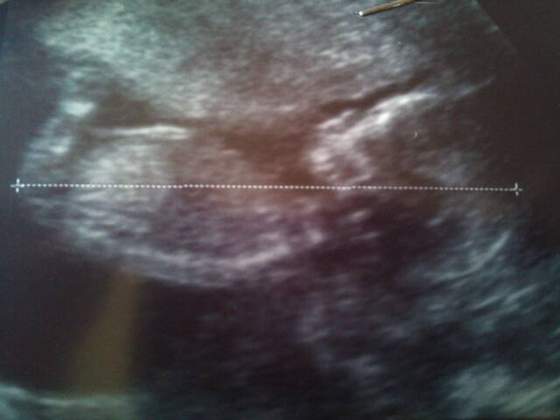

Mozg byl ladnie widoczny,zoladek i reszta tez.Na sam koniec babka powiedziala ze jest bardzo uparty bo nie dal sie zmiezyc.Wyczepala go na wszystkie mozliwe sposoby a dzidzi i tak nie zmienilo pozycji

Na koniec chyba jednak sie zlitowalo bo w koncu zmienilo pozycje